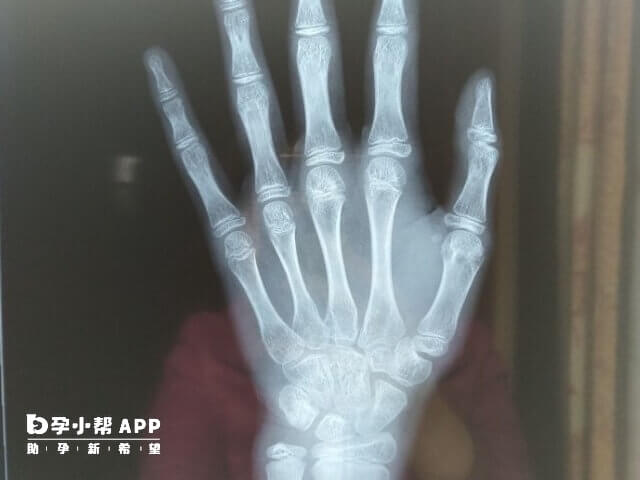

骨齡是骨骼年齡的簡稱,骨齡和年齡不一定一致,它代表的是骨成熟度,反映的是生物年齡。骨齡需要藉助於骨骼在X射線攝像中的特定影象來確定,通常要拍攝人左手手腕部的X射線片,醫生通過X射線片觀察左手掌指骨、腕骨及橈尺骨下端骨化中心的發育程度進行評估。下面是10-16歲兒童的骨齡身高表,大家可以參考: